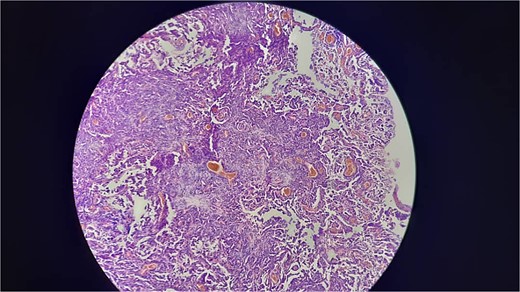

A 38-year-old male educator and part-time farmer with no notable cancer history in his family and a non-smoking background sought medical attention. His medical records included a left inguinal hernia repair two years prior and an ischemic stroke six years ago, for which he was undergoing ongoing treatment with clopidogrel, aspirin, and rosuvastatin. The patient reported swelling in the right inguinal region, without any other symptoms. The patient was prepared for surgery to repair the hernia. Upon opening the hernial sac, a thickened wall was observed. Aspiration was conducted to exclude bladder involvement, yielding cloudy, serous fluid indicative of ascites and omental thickening. Based on these observations, samples from the hernial sac wall (peritoneum), omentum, and ascitic fluid were submitted for histopathological analysis, and the hernia was repaired (Fig. 1). Peritoneal surgical biopsy showed that the peritoneal tissue fragments involved epithelioid cell malignant neoplasms with tubular and papillary formations and stromal infiltration. An IHC study revealed Calretinin and CK5/6 markers (mesothelial cell markers) were diffusely positive in the tumor, leading to a diagnosis of malignant mesothelioma. (Fig. 2 and 3) CEA levels were assessed and found to be within the normal limits. Contrast-enhanced computed tomography (CT) of the chest, abdomen, and pelvis revealed a 58 × 31 mm lobulated mass with multiple septate cavities in the lateral and basal pleura of the left lower lobe (Figs 4–6). The scan also showed thickening of the omentum, mesentery, and peritoneum, consistent with a left pleural mesothelioma with peritoneal and omental metastases. Oncologists diagnosed the patient with stage 4 pleural mesothelioma. The patient was determined to require oncological treatment consisting of eight cycles of cisplatin combined with gemcitabine. Unfortunately, the patient died during the fourth chemotherapy cycle.

Shows that the neoplastic cells are strongly and diffusely positive for Ck5/6 (membranous and cytoplasmic staining).